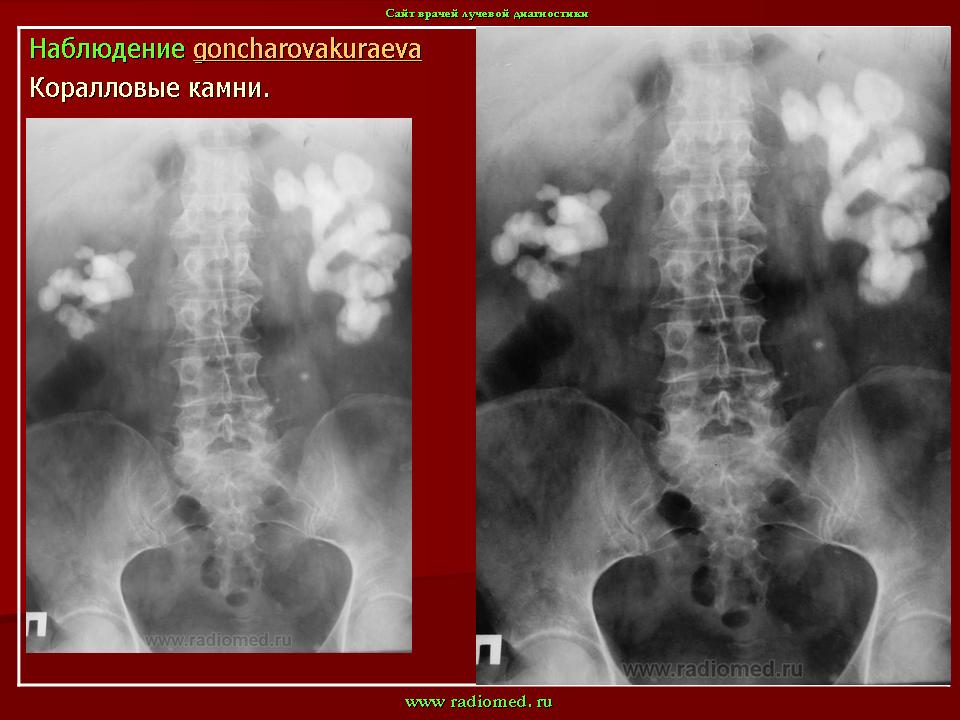

Ваше заключение по снимку// Новообразования почек// Оксолатовые камни почек// Уратовые камни почек// +Коралловидные камни почек// Гидронефроз почек